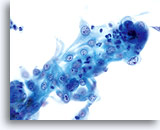

Kernen zijn vergroot, nemen vaak meer dan 2/3 van het cytoplasma in beslag en blijven doorgaans rond tot ovaal, met golvende celkernmembranen.

60x